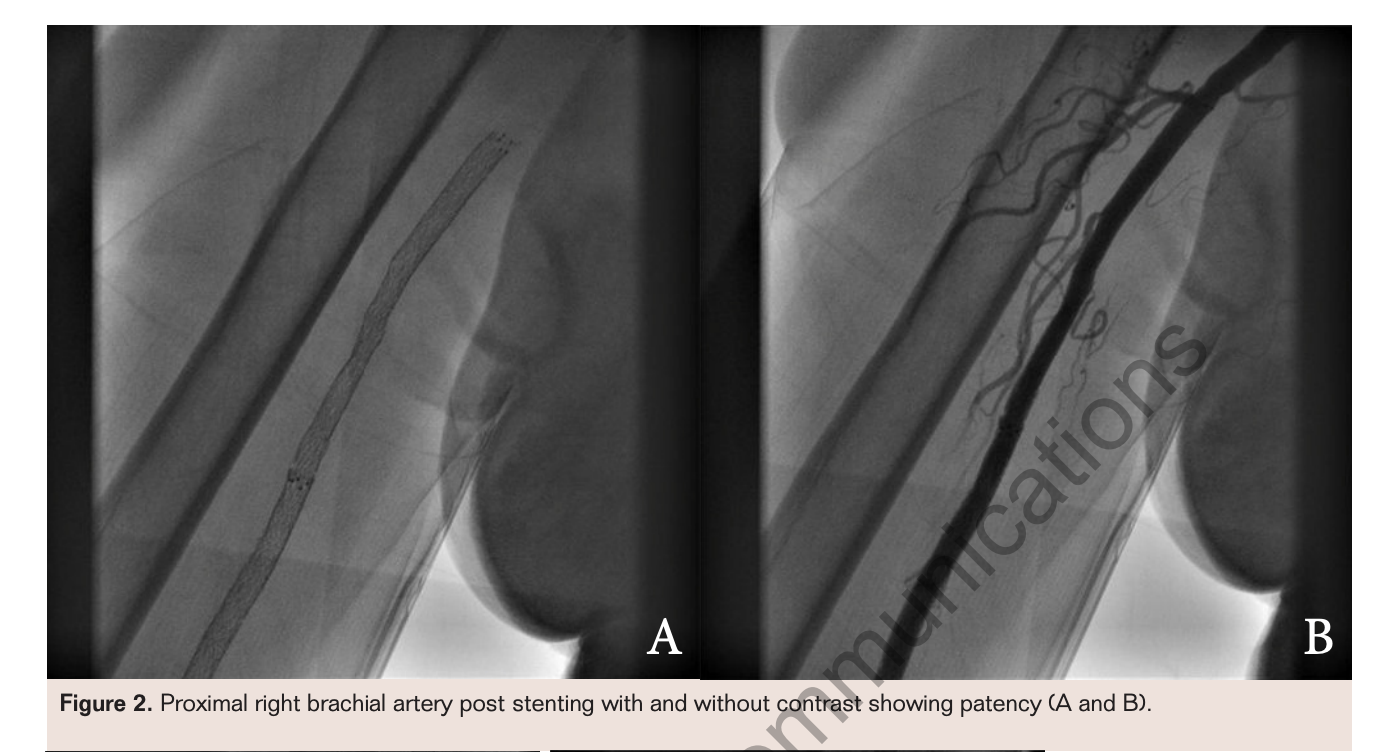

A 79-year-old woman with a past medical history of coronary artery disease and hypertension complained of pain and numbness in her right forearm and hand, increasing in severity. These symptoms had begun 10 months following uncomplicated cardiac surgery, a 2-vessel coronary bypass with 2 vein grafts and with bioprosthetic aortic valve replacement via median sternotomy. Prior to her cardiac surgery, she did have angiography which revealed severe 2-vessel disease including her left main and circumflex arteries, in addition to severe stenosis of her aortic valve. Angiographic approach at this time was via femoral access, and it was decided that the patient would benefit from CABG. Of note, during the surgery she did have an arterial line placed in her right radial artery for routine arterial pressure monitoring, which remained in place for the day following the surgery as well but was removed without complication. In the 3 to 4 months prior to her office visit, the patient stated that her right hand was, at times, cold and that she could not bear to have it uncovered. It was becoming increasingly weak, while the left hand was asymptomatic. On examination her right hand was pale and cool, and there were no palpable brachial, radial, or ulnar pulses. Prior to heart surgery she had been documented to have had a brachial cuff pressure of 146/80 mmHg on the right and 140/80 mmHg on the left. Radial and ulnar pulses had been 2+ on the right preoperatively. Noninvasive testing including a Doppler ultrasound of her right upper extremity at this time was consistent with stenosis of her brachial artery, and she was scheduled for angiography (Figure 1).

Angiography via a right femoral artery approach revealed a severe stenosis of the proximal right brachial artery with what appeared to be a dissection plane extending to above the elbow. A 6 Fr JR4 guiding catheter (Cordis) had been placed into the right axillary artery using an angled Glidewire (Terumo). Aspirin and intravenous heparin had been administered. After angiography a 0.014" 300 cm BMW Universal wire (Abbott Vascular) had been placed and ultrasound imaging was attempted in the proximal brachial artery, but an Eagle Eye Gold Catheter intravascular ultrasound catheter (Volcano) would not pass into the diseased segment. The catheter was exchanged for a 4 mm x 120 mm Fox sv PTA catheter (Abbott Vascular) and dilatation performed at 4 atm for 20 seconds and more proximally, overlapping, at 4 atm for 38 seconds. However, the angiographic result revealed concerning luminal narrowing following angioplasty. Therefore, the balloon was replaced for a Quick-Cross 0.035" x 135 cm support catheter (Spectranectics) to enable placement of a 0.035" x 260 cm Rosen wire (Cook Medical) into the radial artery, after removal of the BMW Universal wire.